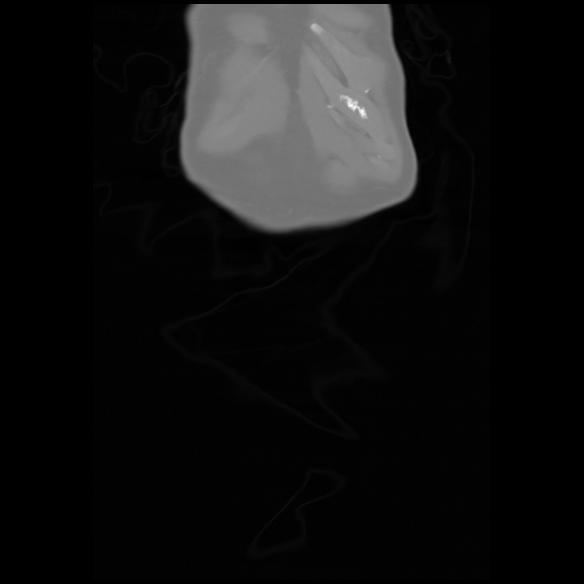

6 CUERPO,CE,Coronal,3.000,CUERPO,Coronal,